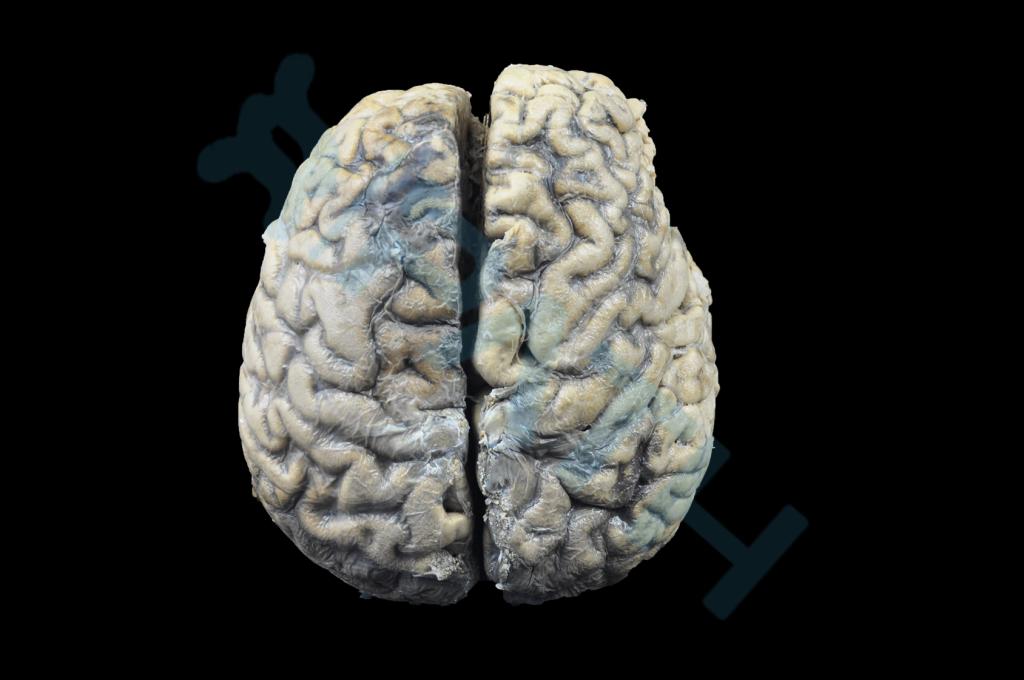

神经系统疾病

脑脓肿(2)

出血性脑膜炎(炭疽病)